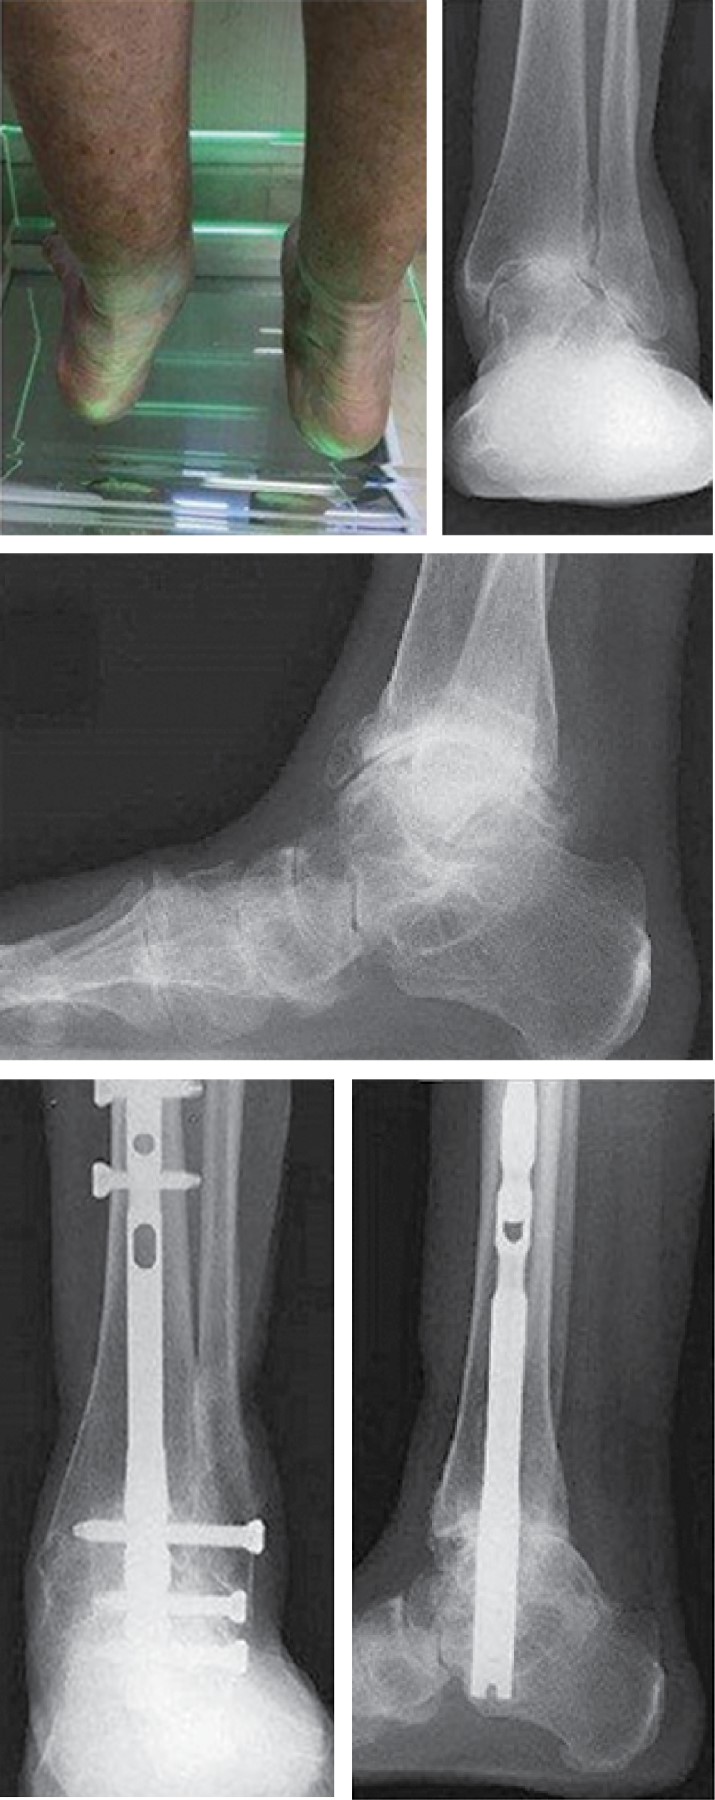

Figure 4